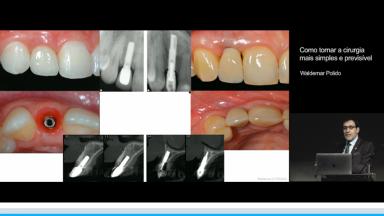

Surgical Planning and Procedures

Como tornar a cirurgia mais simples e previsível

Waldemar Daudt Polido

A apresentação demonstra fatores de risco relacionado ao resultado protético com implantes. Ressalta as expectativas dos pacientes no tratamento e como planejar procedimentos cirúrgicos de forma a se aproximar destas expectativas. Para isso, são destacados a importância do conhecimento da anatomia do rebordo alveolar, e como seus defeitos de tecidos duros e moles impactam a morfologia dos tecidos perimplantares. Também, são discutidos estratégias para obtenção de estabilidade através de técnica cirúrgica, conhecimento da macrogeometria e tecnologia de superfície. Além disso, a relevância da  posição ideal para estabilidade tecidual, e como o planejamento virtual e guias cirúrgicas podem auxiliar na obtenção da posição 3D são esclarecidas. Por fim, são descritos também o papel do volume de tecidos duros e as possíveis complicacões relacionadas a erros de planejamento.